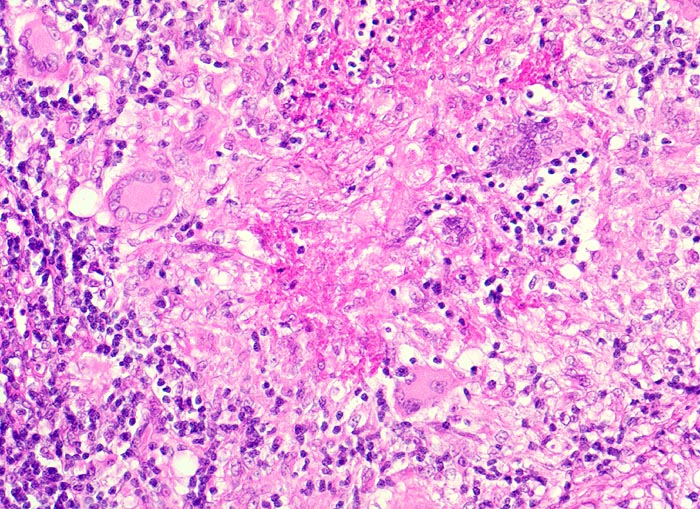

Morphologische Merkmale:

• Lymphknoten mit ausgedehnten konfluierenden eosinophilen Nekrosezonen und nur wenig erhaltenem Lymphknotengewebe (blau).

• In den grösseren Nekrosearealen sind Kerntrümmer von neutrophilen Granulozyten erkennbar.

• Demarkierung der Nekroseareale durch schlanke Epitheloidzellen, Riesenzellen vom Langhanstyp mit hufeisenförmig angeordneten Kernen und Lymphozyten.